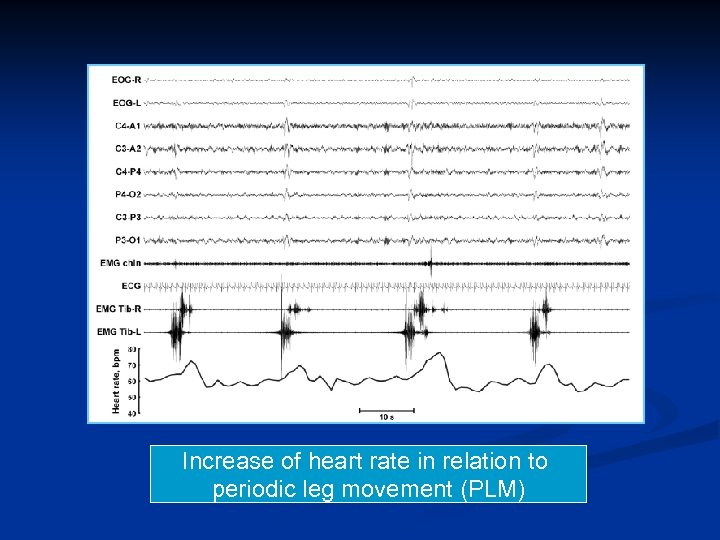

Increase of heart rate in relation to periodic leg movement (PLM)

RLS and periodic limb movements In RLS, PLMs induce a repetitive rise in blood pressure and heart rate Pennestri MH, et al. Neurology 2007; 68: 1213– 1218. Siddiqui F, et al. Clin Neurophysiol 2007; 118: 1923– 1930.